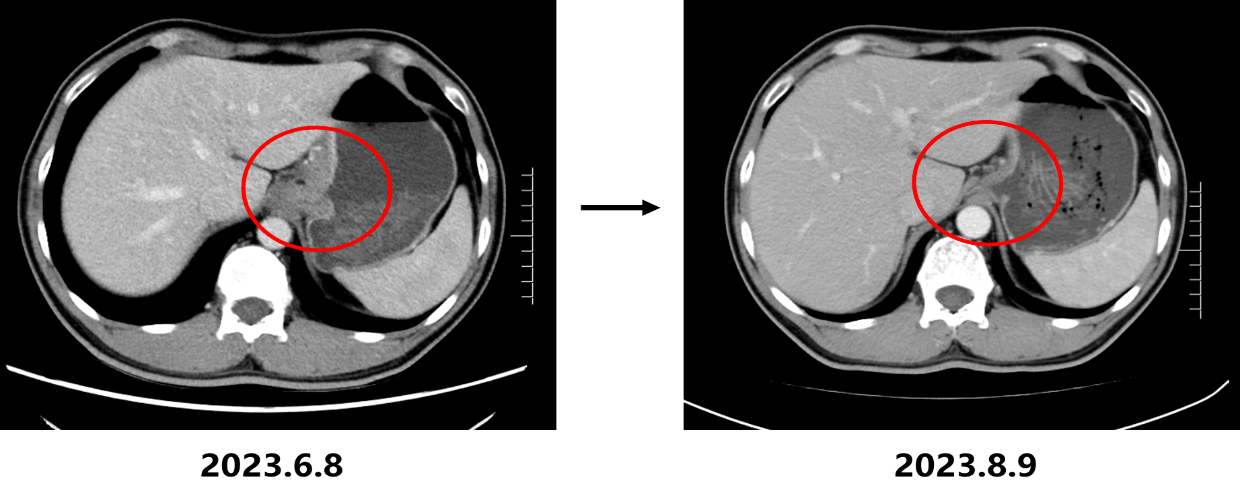

• 2023.8.10复查CT:胃底贲门部胃壁增厚明显改善,肝胃间隙及腹膜后多发淋巴结转移瘤较前缩小(大者短径17mm)、双肺多发转移瘤较前缩小、减少,疗效评估为部分缓解(PR)。